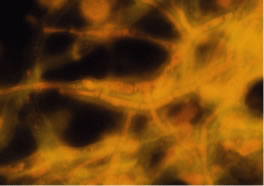

In the early stages of infection, filamentous fungi produce signs that are readily distinguishable from yeast or bacterial keratitis. The most distinctive sign is the presence of delicate, fine, feathery, opalescent, gray-white or yellow-white material in the anterior stroma, surrounded by scant cellular infiltrate or edema (Fig. 1). The epithelium may be intact. The overlying epithelium may be granular and the surface elevated and irregular in contour. Linear infiltrates typically extend into the adjacent stroma. Multiple discrete opacities may develop outside the perimeter of the principal focus of inflammation, either separated by clear stroma or linked by fine linear collections of inflammatory cells and material (Figs. 2 and 3). In the absence of inflammation in the adjacent stroma, branching hyphal fragments may be visualized by biomicroscopy (Figs. 4 and 5). Confocal microscopy may also detect hyphal elements within the stroma.28,29 Peripheral infection resembles noninfectious marginal infiltrative and ulcerative keratitis (Fig. 6). Multifocal keratitis may develop after contact lens wear or injury by multiple projectiles (Fig. 7). In the early stages, iritis is present and the intraocular pressure remains normal. Inappropriate, empirical therapy of fungal keratitis with topical fluoroquinolone or aminoglycoside antibiotics may suppress or eliminate the superficial elements but allow extension of the organisms into the stroma because these agents may possess selective antifungal activity.4,30,31

There is no distinguishing clinical sign by which to recognize the genus or species of the infectious filamentous fungus. F. solani is the most virulent organism and typically produces rapidly progressive infection characterized by epithelial and stromal ulceration, dense stromal necrosis, abundant cellular infiltrate, and edema in the adjacent stroma and hypopyon (Figs. 8 and 9). Delicate feathery components are transient. Individual hyphal fragments are rarely visualized. Infection by certain species of Aspergillus and Scedosporium (Figs. 10 and 11) resembles F. solani keratitis and progresses rapidly. Infection by less virulent organisms, such as Curvularia and Alternaria species, produces small, focal (less than 3-mm diameter) areas of nonnecrotizing stromal inflammation with delicate feathery borders (see Fig. 1 and Fig. 12). Macroscopic pigmentation may develop in keratitis caused by Alternaria, Curvularia, and other dematiaceous fungi (Fig. 13).4,11,14 The central component may progress to dense, opaque, gray-white suppuration in the deep stroma without enlargement in total area and may be accompanied by mild inflammation in the adjacent stroma. Iritis is minimal to moderate. Infection caused by other, relatively less virulent organisms resembles herpes simplex or noninfectious keratitis (Fig. 14).